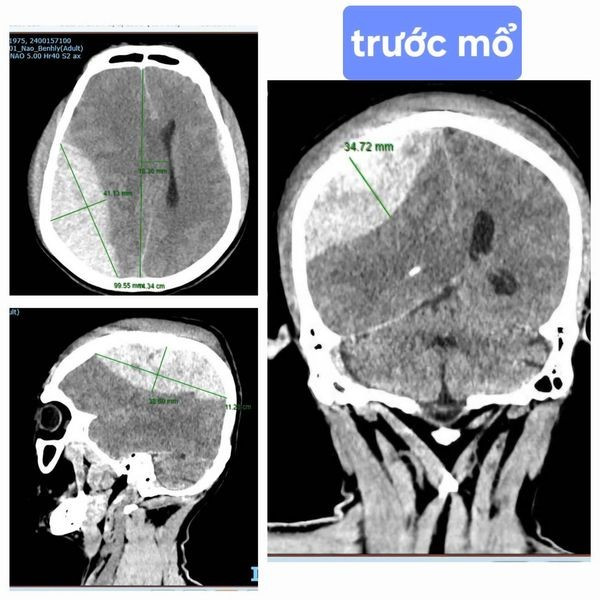

| Hình ảnh phim chụp sau phẫu thuật - Ảnh BVCC |